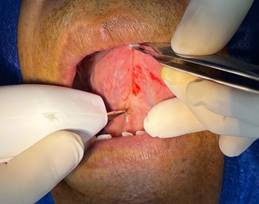

· Diéresis: Se sujetó la lengua con la ayuda de una pinza Adson con dientes, después se utilizó el electrobisturí realizando cortes lineales verticales o ligeramente convergentes hacia apical. (Figura 4)

Figura 4. Diéresis.

Elaboración: Los autores.